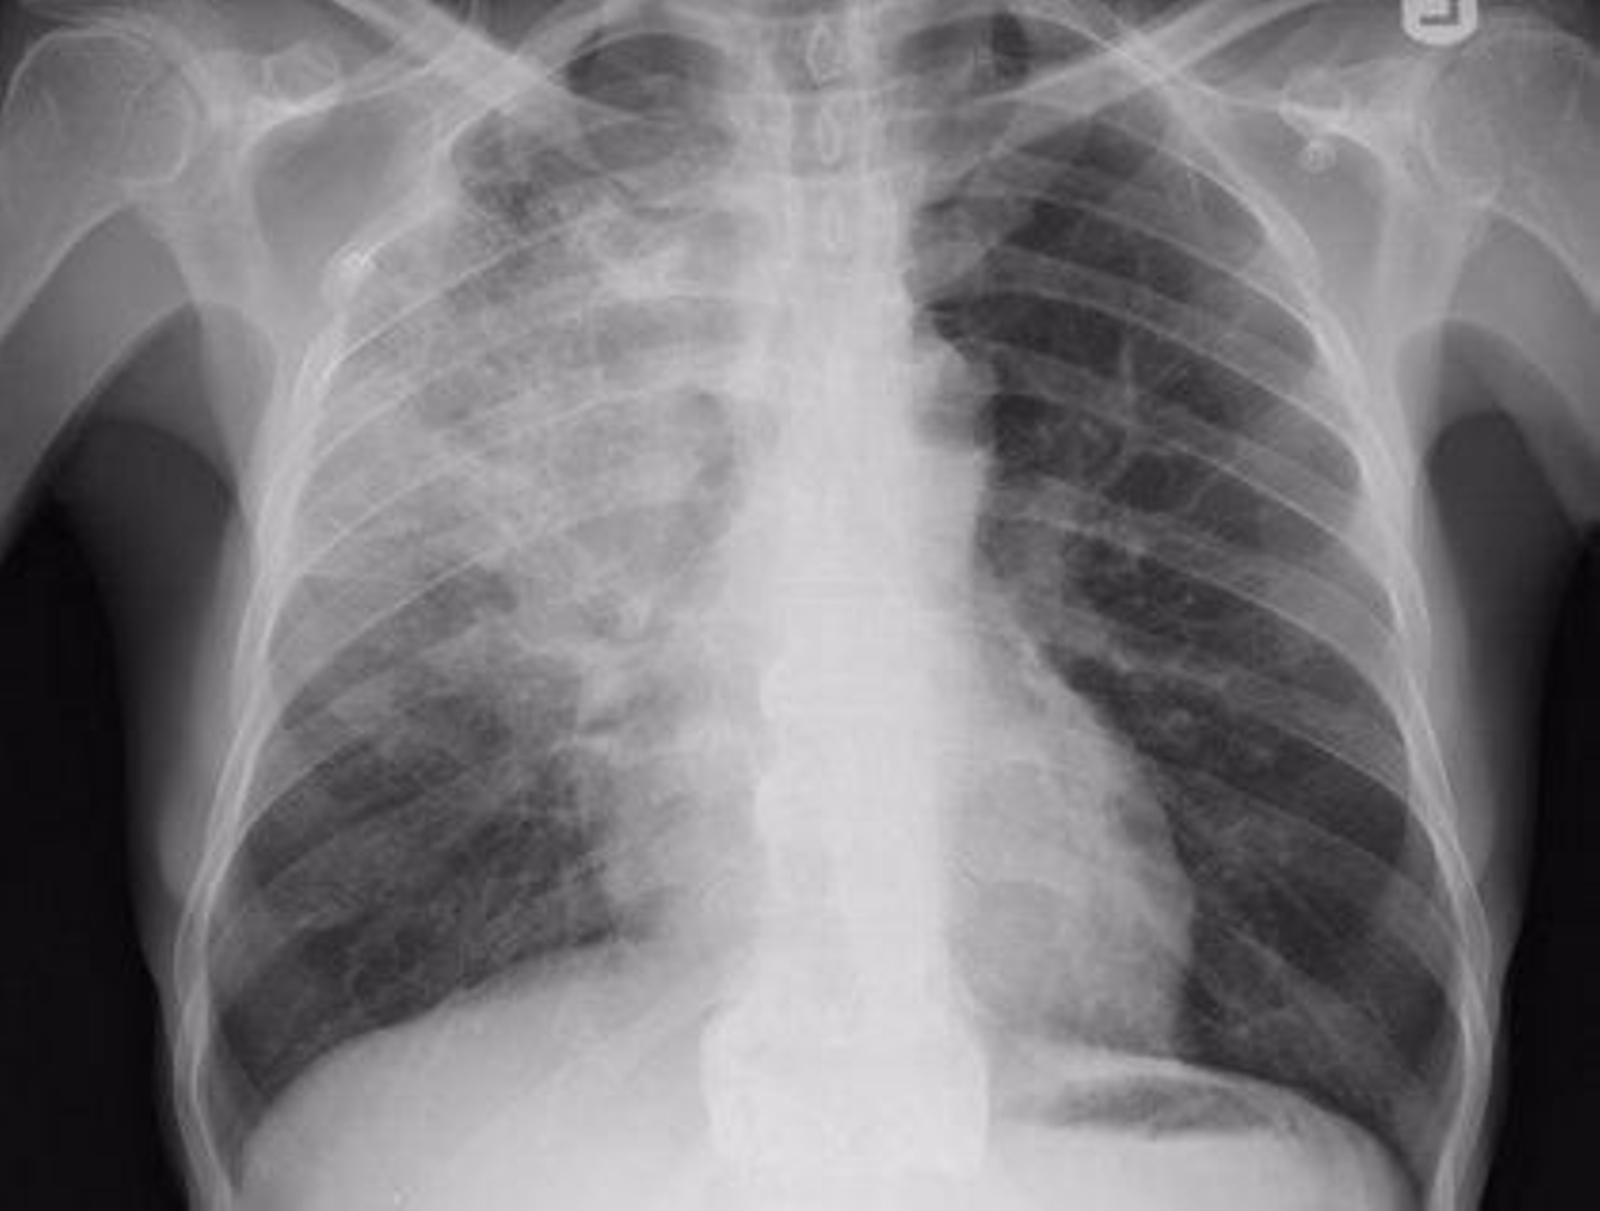

La sintomatología concreta va a depender del sistema afectado por la aparición de granulomas. En el caso de la afectación de pulmón, los pacientes tienen síntomas como disnea, tos, dolor u opresión torácica. Las radiografías de tórax muestran patología casi en un 90% de los casos.

Respecto a su diagnóstico, hasta en un 50% de los casos se puede descubrir de forma casual por hallazgos clínicos-radiográficos y la posterior demostración por biopsia de granuloma caseificantes con cultivos negativos para micobacterias u hongos.